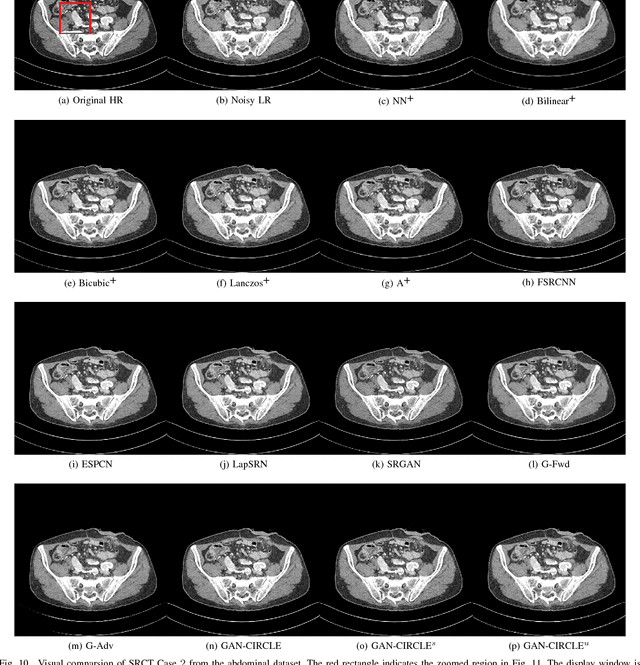

Abstract:Computed tomography (CT) is widely used in screening, diagnosis, and image-guided therapy for both clinical and research purposes. Since CT involves ionizing radiation, an overarching thrust of related technical research is development of novel methods enabling ultrahigh quality imaging with fine structural details while reducing the X-ray radiation. In this paper, we present a semi-supervised deep learning approach to accurately recover high-resolution (HR) CT images from low-resolution (LR) counterparts. Specifically, with the generative adversarial network (GAN) as the building block, we enforce the cycle-consistency in terms of the Wasserstein distance to establish a nonlinear end-to-end mapping from noisy LR input images to denoised and deblurred HR outputs. We also include the joint constraints in the loss function to facilitate structural preservation. In this deep imaging process, we incorporate deep convolutional neural network (CNN), residual learning, and network in network techniques for feature extraction and restoration. In contrast to the current trend of increasing network depth and complexity to boost the CT imaging performance, which limit its real-world applications by imposing considerable computational and memory overheads, we apply a parallel $1\times1$ CNN to compress the output of the hidden layer and optimize the number of layers and the number of filters for each convolutional layer. Quantitative and qualitative evaluations demonstrate that our proposed model is accurate, efficient and robust for super-resolution (SR) image restoration from noisy LR input images. In particular, we validate our composite SR networks on three large-scale CT datasets, and obtain promising results as compared to the other state-of-the-art methods.